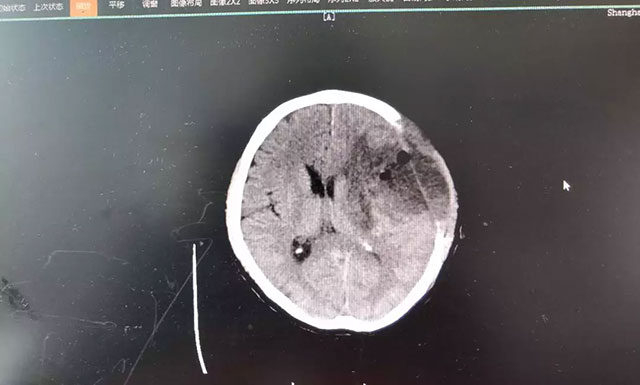

在蓝十字脑科医院,头颅磁共振增强扫描影像进一步明确:钱先生左额颞叶占位性病变,类椭圆形团块状异常信号大小约4.3*3.2cm,边界不清,病灶周围有明显水肿。从症状体征和影像学资料判断,钱先生患上脑胶质瘤的可能性很大,通过对患者术后病理标本检验,也印证了该结论。

▲ 患者术前磁共振增强扫描影像